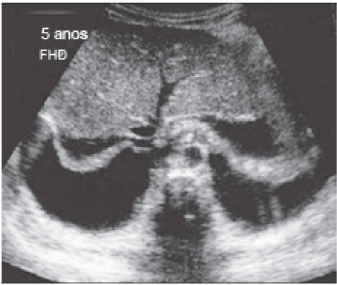

Imagem ultrassonográfica de paciente do sexo masculino, 30 anos de idade, com quadro de dor abdominal difusa, hemograma com leucocitose e radiografia abdominal simples com achados inespecíficos.

Com base nos dados apresentados, assinale a alternativa com a melhor hipótese diagnóstica.